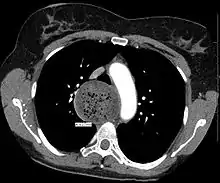

| A chest X-ray showing achalasia (arrows point to the outline of the massively dilated esophagus) | |